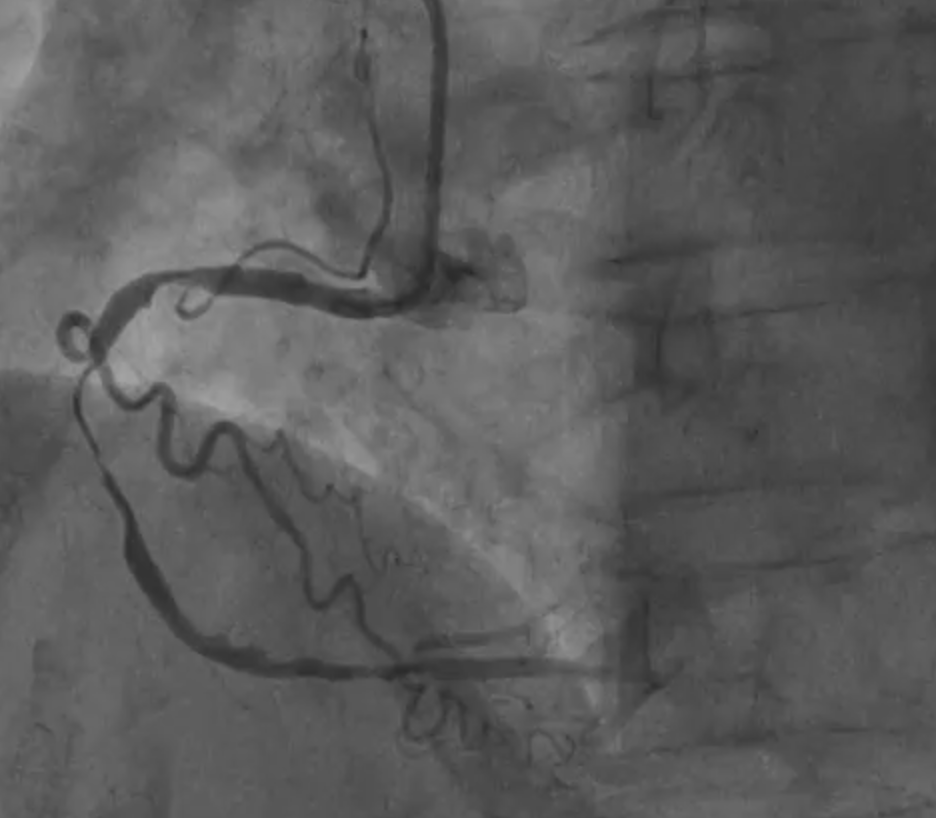

The coronary angiogram, performed via right radial access, revealed a mid-LAD chronic total occlusion (CTO), moderate stenosis in the proximal LCX, and critical stenosis in the mid-RCA. The RCA flow was TIMI 2. We decided to perform PCI on the RCA using the same access route.